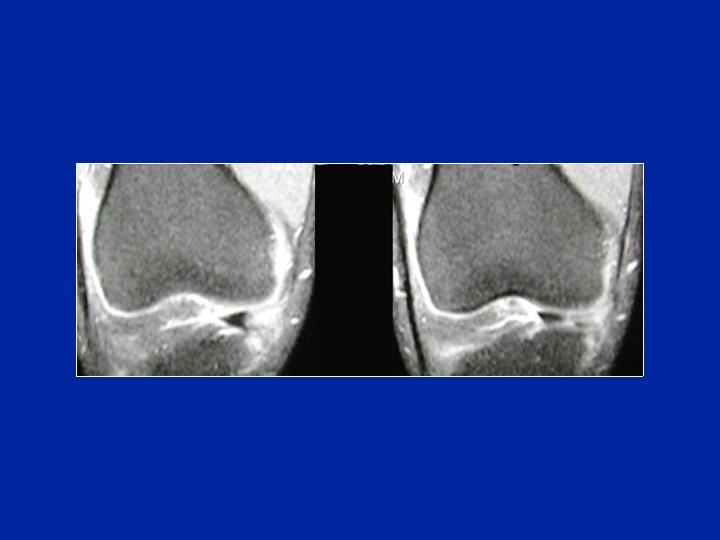

RMN Clasificación de Crues Estadio 1: hiper señal globular intra-meniscal que no afectan a las superficies meniscales Estadio 2: hiper señal lineal intra-meniscal que no afecta a las superficies meniscales Estadio 3: hiper señal lineal intra-meniscal que afecta a las superficies meniscales: fisura Estadio 4: hiper señal compleja intra-meniscal con remanentes de la morfología meniscal: fisura compleja

RMN

RMN Sensibilidad: 62 - 100 % Especificidad: 53 - 100 % Valor predictivo positivo: 59 - 99 % Fisura horizontal Fisura vertical